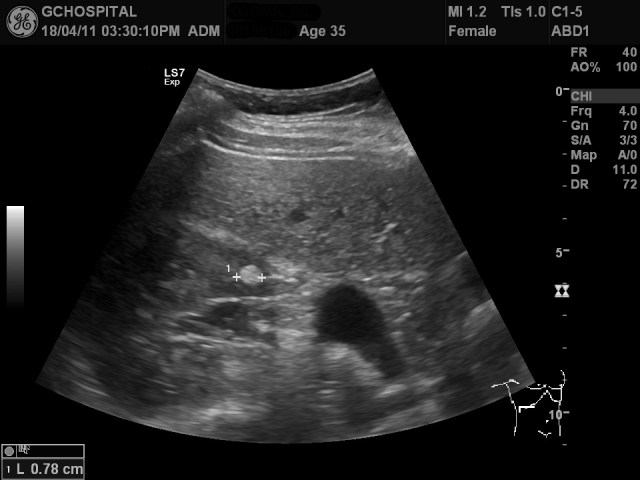

건강검진차 초음파를 시행한 35세 남자환자의 우측 신장에 8밀리미터 크기의 경계가 분명한 고에코음영이 발견되었습니다.

이렇게 1센티미터 이하의 작은 고에코 결절이 신장에 보이면 가장 유력한 가능성이 양성종양의 일종인 angiomyolipoma(AML)입니다. 하지만, 신세포암(renal cell carcinoma)도 크기가 작으면 고에코음영을 보이기 때문에 그 가능성을 배제할 수는 없어 감별이 필요합니다.

이 경우, 결절 내부에 fat component가 존재하는지를 확인하는게 필요하고, 이를 위해서 fat-suppression MRI영상이 필요합니다.